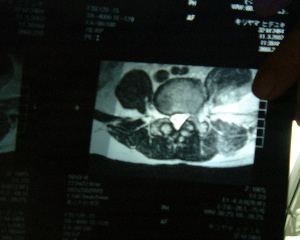

折れた横突起(おうとっき。漢字は不明)周辺を上から見る。右の方が白いのがわかるだろうか。これが内出血で、不具合の原因